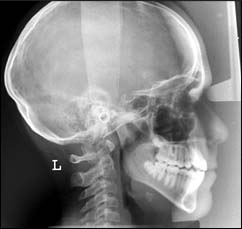

Ces examens sont principalement réalisés dans le cadre d'un traitement ODF ; ils ont pour but de permettre un diagnostic et un pronostic précis pour entreprendre un traitement.